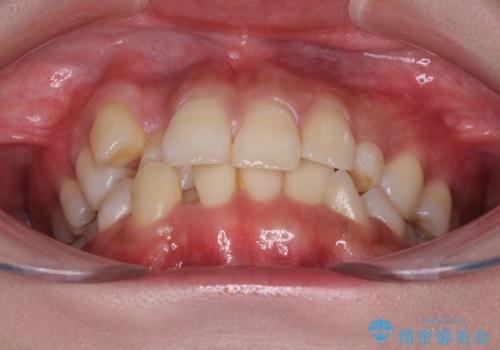

- 前歯のデコボコと残っている乳歯の部分へのインプラント治療を希望して来院された患者様です。

当初は目立たない上下裏側矯正を希望されていましたが、歯並びの悪さによる磨き残しが多く、歯肉炎が認められたため、より清潔な環境で治療を進められるインビザラインを選択することとしました。

前歯のデコボコが強かったため、上の奥歯を後方に動かす量が多くなり、結果として2年以上の治療期間を擁することとなりました。

歯並びが整ったことで治療前に認められた歯肉炎は全くなくなり、患者様には大変満足していただきました。